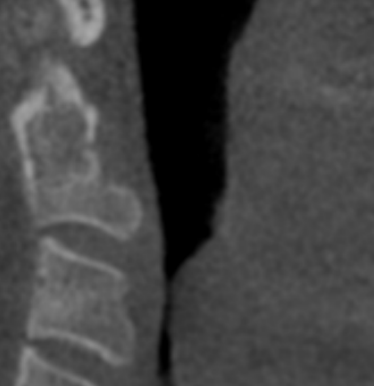

Case 6: Significant narrowing of lower airway noticed. Biopsy identified cancer. Surgery and treatment commenced.

Case 7: It is common to see sinusitis. When the sinus is chronically full with inflamed tissue it leads to pressure pain, blocked passages and higher incidence of infection. Clear sinus on the right is black. Fully occluded sinus on left needs ears nose throat specialist referral.